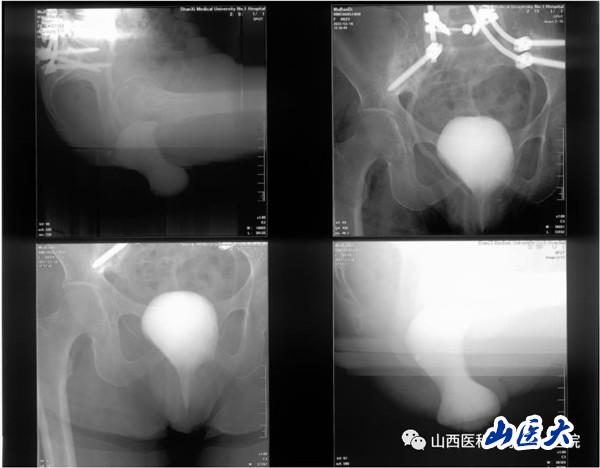

患者女性,62歲,盆腔臟器脫垂合并骶骨缺損,近年來輾轉北京及省內各大醫院尋求外科治療,但均未能如愿。